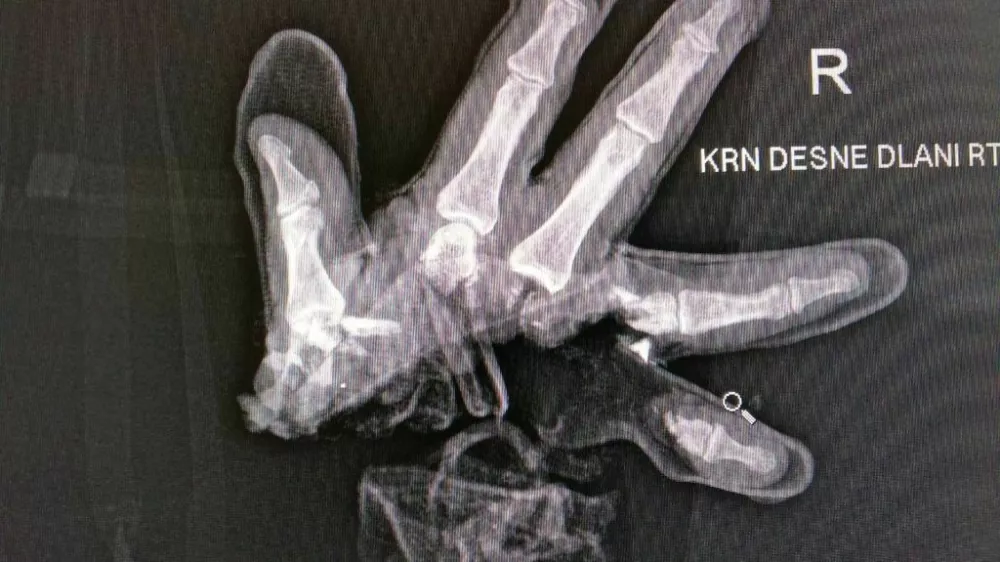

Policisti opozarjajo, da je nepremišljena, neprevidna in objestna raba pirotehnike nevarna, saj lahko povzroči hude poškodbe in ima lahko dolgoročne posledice. V Žalcu se je že na prvi letošnji dan hudo poškodoval 15-letnik, ki je ostal brez dela roke.

Konec lanskega decembra pa smo poročali o hudi poškodbi otroka, ki mu je v rokah eksplodiralo pirotehnično sredstvo. Skupina otrok, mlajših od 14 let, se je družila na igrišču na ljubljanskih Fužinah, ko je eden od njih poskušal prižgati kos pirotehnike. Ta sprva ni delovala, potem pa mu je počila v rokah. Otrok se je zelo hudo poškodoval, zlasti po rokah in obrazu. Na pomoč mu je takoj priskočil mimoidoči, skupaj s policisti je poskušal ustaviti najhujše krvavitve, z reševalnim vozilom pa so ga odpeljali v bolnišnico.

S tovrstnimi nesrečami se ne soočajo samo slovenski policisti, temveč tudi drugod po svetu. Na Hrvaškem so v petek zvečer v bolnišnico v Osijeku pripeljali desetletnega fanta, ki mu je sredi mesta v rokah eksplodirala petarda. Na levi roki so mu morali amputirati dva prsta.